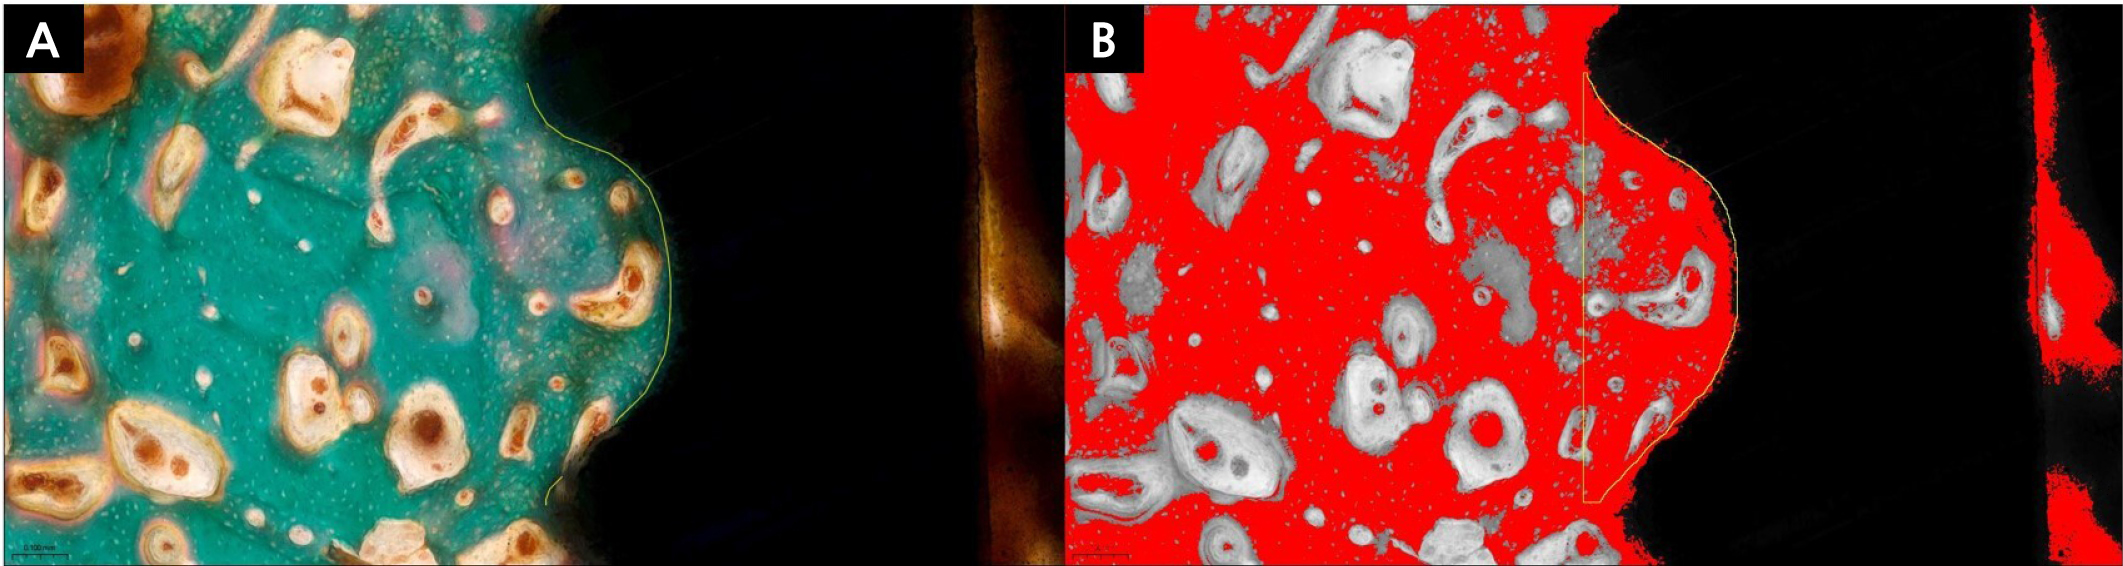

Both BIC and ITBD measurements were independently performed by all examiners using ImageJ software (Fig. 8). Images of stained sections were obtained using a light microscope (BX Series; Olympus, Tokyo, Japan).

Fig. 8

Histomorphometric evaluation of bone-to-implant contact (BIC) and inter-thread bone density (ITBD) in Goldner’s trichrome (GT)-stained sections. Green-stained areas represent bone, red-stained areas indicate muscle-related tissue, and white regions correspond to preparation artifacts. Yellow lines delineate the boundaries of the region of interest (ROI). (A) BIC was measured as the proportion of bone-contact length to the total implant length within the ROI, (B) ITBD was measured as the proportion of bone area within the inter-thread space to the total inter-thread area. Variations in color tones in Panel B resulted from threshold adjustment and image processing in ImageJ, which selectively highlighted bone areas for ITBD analysis.